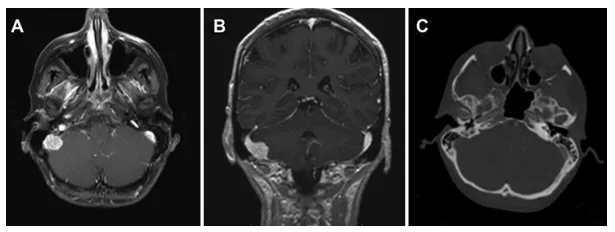

一名36岁女性患者,既往有左颈动脉夹层病史并曾行支架植入术,检查发现右后颅窝存在一个1.6×1.8厘米、均匀强化的硬膜外占位性病变且呈进行性增大。

术前血管成像显示乙状窦部分闭塞伴可疑肿瘤侵犯(图2)。

病例2,术前轴位(A)与冠状位(B)增强T1加权磁共振图像显示右侧后颅窝一类圆形、均匀强化的轴外病变,并延伸至乙状窦内。术前轴位脑CT血管成像(C)显示右侧乙状窦因肿瘤压迫侵犯致部分闭塞。